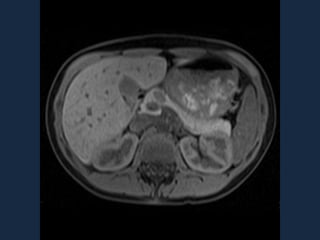

Ecografía endoscópica

Detecta el 77% de los insulinomas en el páncreas su rendimiento es mayor en

combinación con la TC. Tenga en cuenta lo siguiente:

1.- En tiempo real la Ecografía transabdominal de alta resolución tiene una sensibilidad

del 50%.

2.- La Ecografía Intraoperatoria Transabdominal de alta resolución detecta más de 90% de

los insulinomas.

Realización de un estudio preoperatorio para localizar el tumor seguida de la ecografía

intraoperatoria y un examen físico no es irrazonable.

a) la apariencia típica de la USE insulinoma: una masa de 1,5 mm

hipoecoica bien definido en la mitad del cuerpo del páncreas. (B) Dos

insulinomas muy pequeñas (flechas) que mide menos de 5 mm en el

páncreas distal.